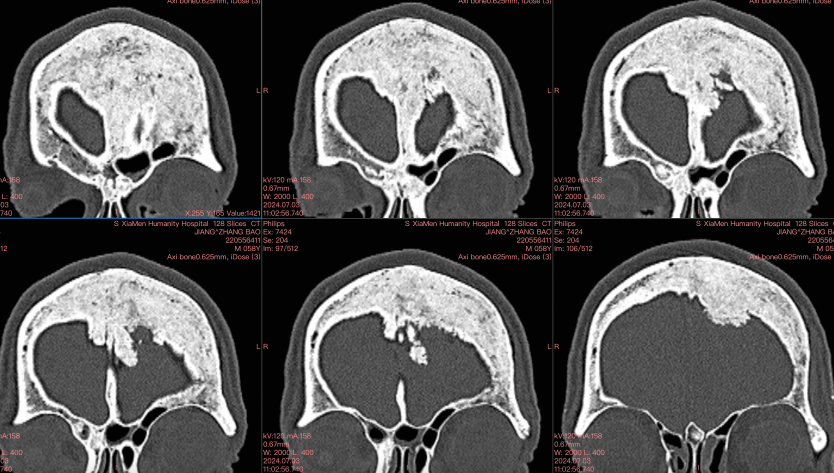

CT

影像重建

CT重建

左額內外板可見骨質增生

顱骨全層受累病變

①顱骨內板增生

②顱骨外板受累

③顱骨全層增厚